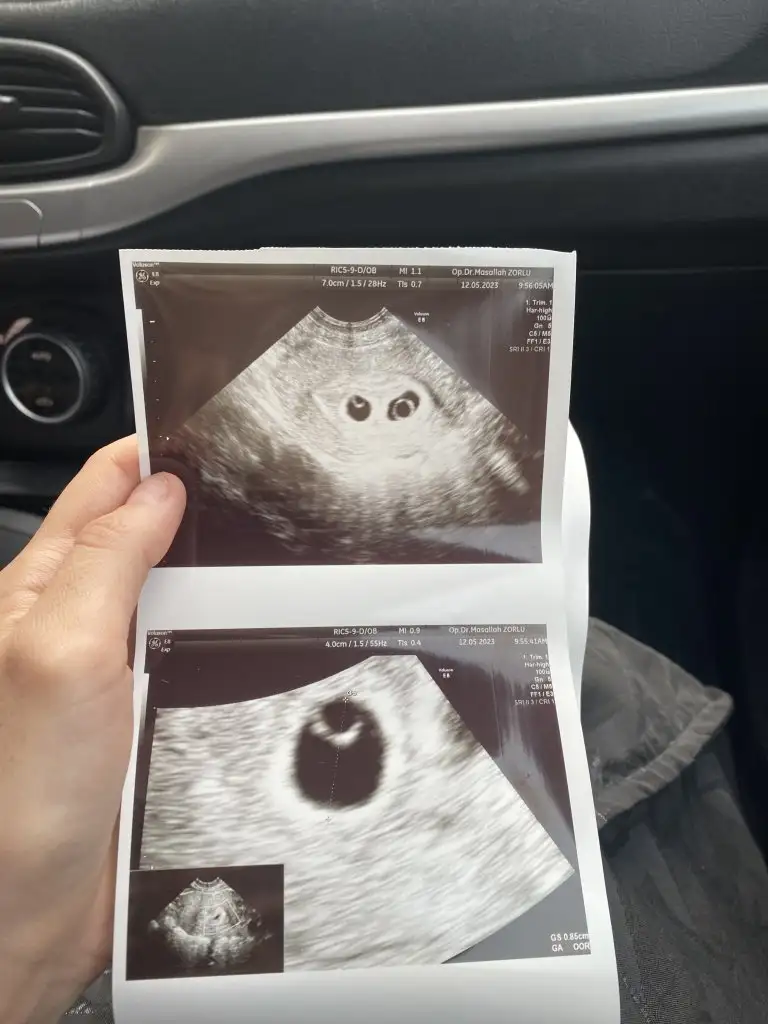

Resimde çok net değil ama alttan muayene de böyle kese içinde yuvarlak bşr yüzük şeklinde gözüyor çember gibi köşede. Oda ancak bu zamanlar da oluşuyormuş dedi. Kaç gün önce de varmış ama onda çok net değilmiş demekatarım yarın buraya

Bugün bebeği ve kalp atışını gördük çok şükürBen direk alttan muayene etmesini istedim çünkü karından çok küçük olduğu için görünmüyorlar genelde aslında aletlerle de alakalı iyi bir aletse bence karından da rahat görünüyor iyi hastanelerin. Evet benim de bildiğim kadarıyla o yuvarlak siyah halkın etrafındaki beyaz Çember yok kesesi deniliyor muş ben de çok bilmiyorum benim de bundan önce bir kimyasal bir normal kaybım olmuştu. O yüzden biraz tedirginim ama inşallah güzel sonuçlar alacağız güzel düşünmek lazım sizinde güzel haberleriniz olur mutlaka buradan haberleşelim

Ya çok sevindim hakkınızda hayırlısı olsun inşallah ben de bugün gittim kalp atışını gördüm iki kasa vardı biri diğerine göre daha küçük olduğu için onu birkaç gün sonra duyabiliriz dedi ama ben Vajinal muayene değil yani ama bundan sonrakileri karından yaptırmayı düşünüyorum korkuyorum çünkü Vajinal de bir sıkıntı çıkar diye bir de idrarda protein kaçağı varmış ve tiroitim çok az yüksek çıkmış onun için yarın özel hastane randevu aldım bakalım ilaç başlayacağım sizlerde dikkat edin tahlillerinizi yapın aksatmayınBugün bebeği ve kalp atışını gördük çok şükür

Ya çok sevindim hakkınızda hayırlısı olsun inşallah ben de bugün gittim kalp atışını gördüm iki kasa vardı biri diğerine göre daha küçük olduğu için onu birkaç gün sonra duyabiliriz dedi ama ben Vajinal muayene değil yani ama bundan sonrakileri karından yaptırmayı düşünüyorum korkuyorum çünkü Vajinal de bir sıkıntı çıkar diye bir de idrarda protein kaçağı varmış ve tiroitim çok az yüksek çıkmış onun için yarın özel hastane randevu aldım bakalım ilaç başlayacağım sizlerde dikkat edin tahlillerinizi yapın aksatmayın

Hadi diğerinin de kalp atışını görürsün inşallahYa çok sevindim hakkınızda hayırlısı olsun inşallah ben de bugün gittim kalp atışını gördüm iki kasa vardı biri diğerine göre daha küçük olduğu için onu birkaç gün sonra duyabiliriz dedi ama ben Vajinal muayene değil yani ama bundan sonrakileri karından yaptırmayı düşünüyorum korkuyorum çünkü Vajinal de bir sıkıntı çıkar diye bir de idrarda protein kaçağı varmış ve tiroitim çok az yüksek çıkmış onun için yarın özel hastane randevu aldım bakalım ilaç başlayacağım sizlerde dikkat edin tahlillerinizi yapın aksatmayın